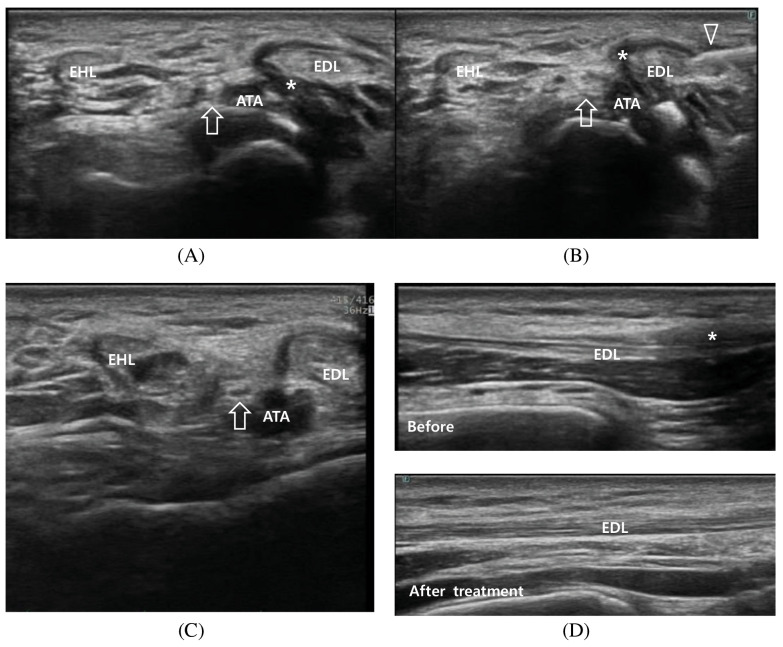

We describe the case of a 41-year-old Asian man who was initially given a diagnosis of peroneal neuropathy but who later received a diagnosis of tenosynovitis of extensor digitorum longus (EDL). The patient initially presented with left lateral ankle numbness, pain, and decreased range of dorsiflexion after an 8-km walk. Peroneal neuropathy was first diagnosed on the basis of reduced compound muscle action potential (CMAP). Conversely, ankle ultrasound revealed normal peroneal nerve but considerable EDL tenosynovitis. Ultrasound-guided injection of triamcinolone and lidocaine into the tendon sheath was performed for pain relief. At 1-month follow-up, CMAP amplitude was restored, and ultrasound imaging revealed normal EDL structure without signs of tenosynovitis. This case serves as a reminder that clinicians must pay attention to multiple factors affecting CMAP, including tendinopathy and pain, to avoid misinterpretation.